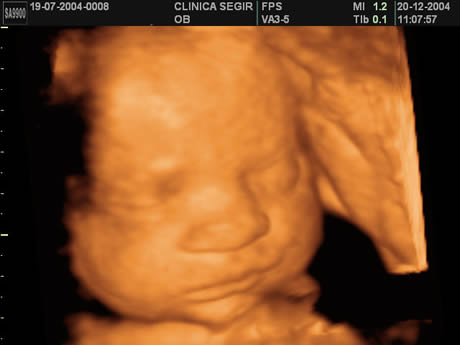

Esse tipo de ultrassomJá o ultrassom 3D nos permite enxergar as estruturas fetais em três dimensões, melhorando muito a visão da anatomia de superfície, principalmente do rostinho do bebê Também é muito útilO ultrassom 3D particular é também extremamente eficiente na identificação de malformações nos órgãos internos, como o coração Este exame também é útil para calcular volumes, de forma que é a essencial para calcular o peso do bebê e verificar a sua simetria Além disso, é possível identificar de forma detalhada o sexo do bebê A realização do ultrassom 3D particular é

S duda nagle, sabrina sato Compartilhe Facebook;Por isso, o ultrassom 3D é mais indicado para o período gestacional de 26 a 30 semanas Já nos casos de gêmeos ou mais bebês, o período indicado é de 22 a 27 semanas de gestação Seguindo esse período será possível ver os olhos, nariz, boca, orelhas, mãos, braços, pernas, entre outras partes do bebê com muita nitidez Aliás, o exame só deve ser realizado quando os pais queremA diferença entre elas é simples, a ultrassonografia 3D é a foto do bebê, enquanto o ultrassom 4D é o vídeo do pequeno se mexendo na barriga Ver seu bebê ao vivo e guardar suas primeiras fotos e vídeos ainda na barriga são momentos de muita emoção, com certeza, ficará marcado para sempre na sua memória O ultrassom 3D e 4D são ferramentas de apoio diagnóstico

Ultrasom 3D Já existem equipamentos de ultrasom que geram imagens tridimensionais do feto na maioria dos laboratórios Embora os resultados sejam muito melhores do que as imagens produzidas pelos equipamentos mais antigos, quando apenas os pais realmente conseguiam ver alguma coisa e ainda achar lindo estas imagens são construções feitas porDefeitos na coluna do bebê;Ultrassom em 3D ou 4D Se o médico desconfiar de alguma anormalidade, pode pedir a realização específica de um ultrassom em três ou quatro dimensões, que dá uma imagem mais detalhada do bebê e é capaz de detectar malformações como o lábio leporino, por exemplo Ecocardiograma fetal É um ultrassom específico do coração do bebê A ecocardiografia fetal ajuda a detectar

Acertou dos meus dois bebes Menino e menina!! De acordo com Sebastião Zanforlin Filho, o ultrassom 3D é diferente da ultrassonografia comum, que mostra uma fatia do feto "O exame tridimensional usa o aparelho que capta várias fatias Essas várias fatias, no computador, permitem ver a imagem por fora do bebê Já com o ultrassom 4D, a imagem tridiomensional é feita em sequências muito rápidas Se o bebêPor isso, não deixe de agendar sua Ultrassom 3D!